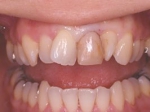

インセラム(オールセラミック)冠による修復。 主訴は前歯が汚い 金属を使わないオールセラミックでの治療を勧めた。 術前

術後